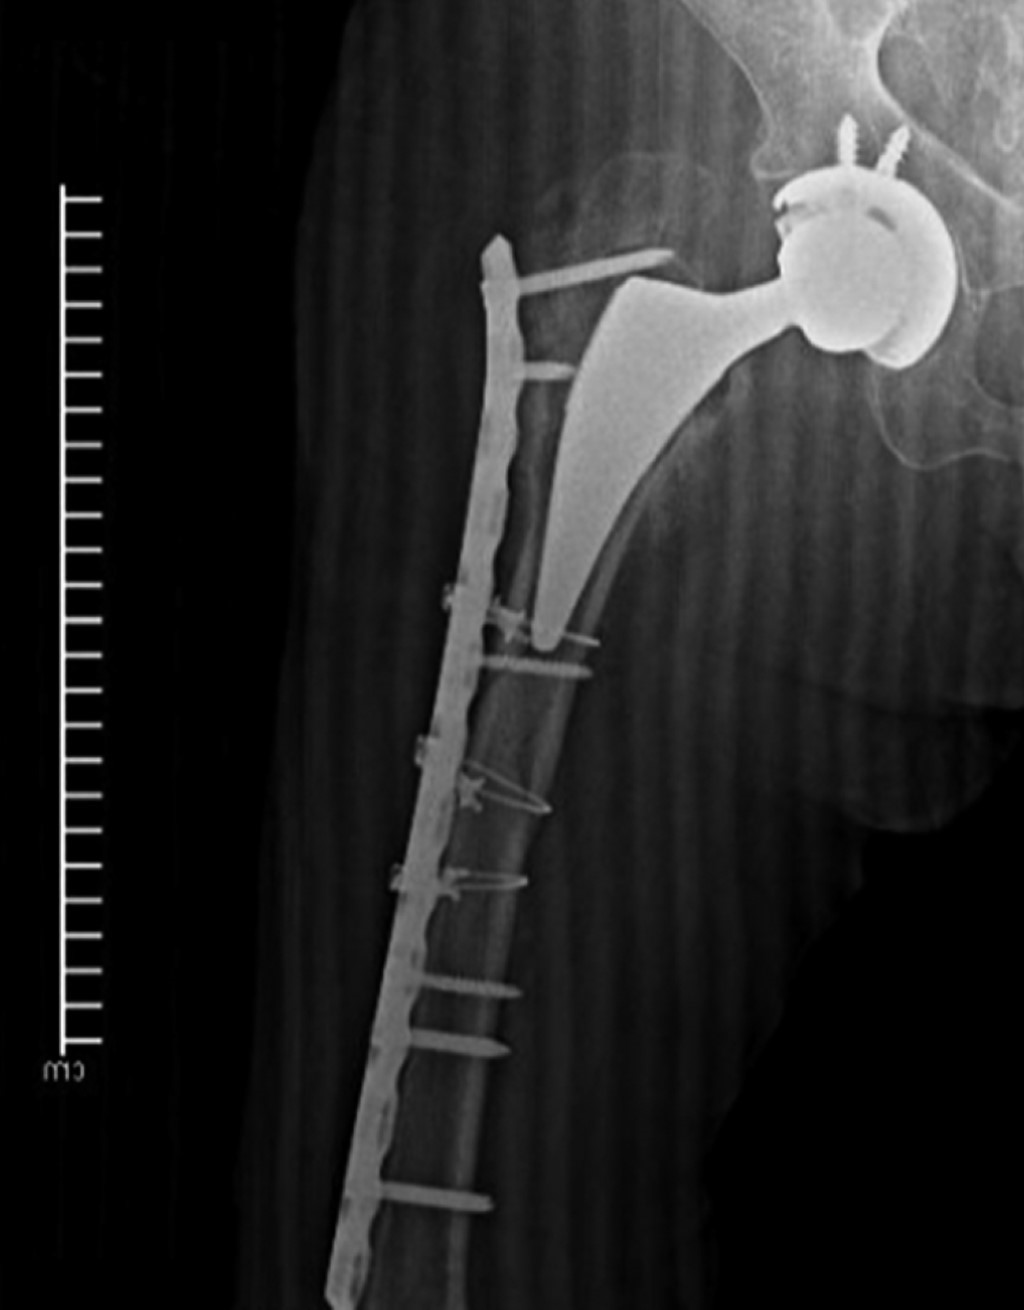

Periprosthetic fracture in a patient with polio sequelae: a case report

Introduction: poliomyelitis paralyzed thousands of children during the 20th century. However, due to mass vaccination its eradication was achieved. Today it is estimated that there are 12 - 20 million people with polio sequelae (PWPS) who make up a risk group for pathological fractures, as a consequence of muscle degeneration and osteopathy. There is no consensus on its treatment. The aim of this report is to demonstrate the problem of fracture management in PWPS. Additionally, an option for the treatment of a periprosthetic fracture in this population is proposed. Presentation of case: 46-year-old male PWPS with pain in the right lower extremity after falling from a chair, with a history of right hip arthroplasty six months ago due to a transcervical fracture. Radiographically, a Vancouver C periprosthetic fracture is seen. Open reduction of the fracture is performed and an anatomical cable-type locking compression plate and cerclage cables are placed. An adequate radiographic evolution is observed. Conclusions: polio is an eradicated disease; however, it should not be ignored since PWPS are a risk group for fractures in pathological terrain. Treatment of these types of fractures and their complications is a challenge. There is a pressing need for comprehensive clinical and surgical guidelines to guide their approach.

Figure 2